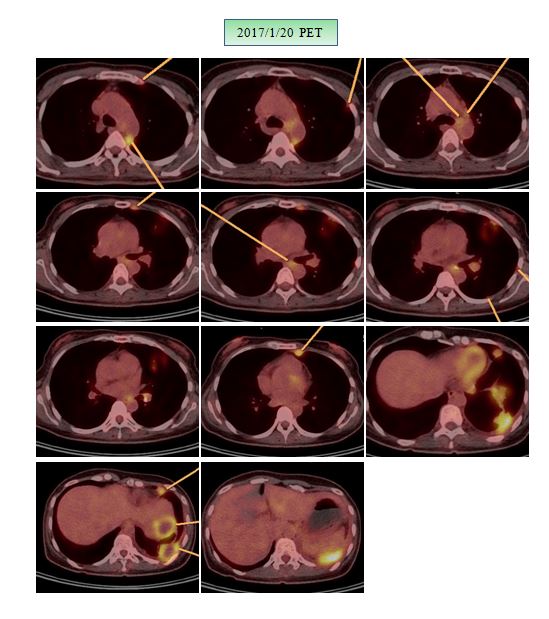

이를 더 쉽게 이해하기 위해서 당시 2017 년 1월 7일 PET를 소개해 본다.

위의 사진에서 보는 검은 점들이 PET 상에서 볼 수 있는 암의 부위로 가슴 쪽에 흩어져 있는 점들이 internal  mammary와  mediastinum의 림프절이고 좌측 늑간 부위가(화살표) 매우 심하게 검은 조영으로 드리워져 있다. 그리고  아래 쪽의 신장 위치에는 약물이 흘러내려가는 것이라 방광과 더불어서 종양이 아니다. 또한 비전문가들의 이해를 돕기 위해서 SUV max라는 개념을 말하면 조영증강의 정도를 말하는 수치로 5 이하면 보통 염증반응이 많고  5 이상이면 암이라고 판단한다. 염증이나 종양이나 모두 새로운 혈관이 재생 혹은 암의 성장을 위하여서 자라기 때문에  PET 상에서는 모두 검게 나타나지만 이 수치를 따져서 암과 염증을 구분한다. 그리고 좌측에 보이는 검은 점은 흉막전이로 이는 늑간 신경이 지나가는 곳으로 굉장히 통증을 동반한다. 아래에  PET CT의 transverse image를 보면 더 쉽게 종양의 상태를 이해할 수 있다. 노랗게 밝은 부분이 위장만 빼놓고 모두 종양으로 볼 수 있다.

아직 항암은 시작하지 않았기 때문에 이 환자의 좋은 결과는 결국 2월 14일부터 시작한 일주일간의 방사선 치료와 한달간의 한약치료 그리고 정확한 식이요법으로 볼 수 있다. 결과는 물론 2월 21일의 PET  결과이므로 지금은 조금 더 좋아졌으리라고 생각한다.

tongue-7.JPG위의 설명대로 아직은 좌측 옆구리에 검은 점들로 보여지는 seeding nodules이 남아 있고 종격동 부위에도 보이지만 이는 SUVmax가 낮아서 언급이 안 되었고 사진상 보이는 것처럼 현저한 치료 전과 후의 차이를 보이고 있다. 이전 폐와  mammary lymph node들에 보이던 음영이 현저히 사라져 소실되었다. 그래서 단지 좌측 폐의 하엽 부위만이 소견서에 언급되었다.